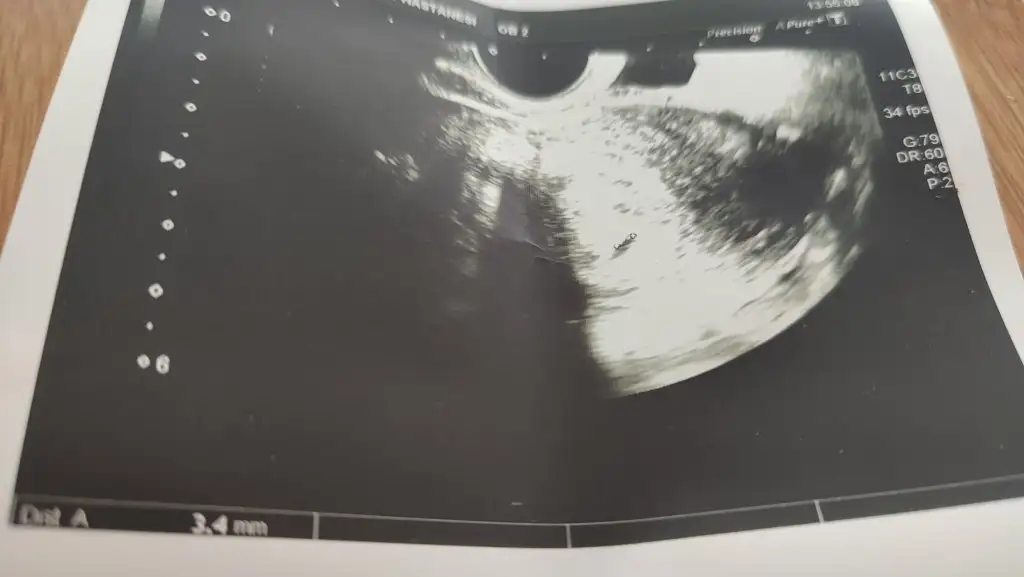

1698 olmuş güzel yükselmiş minik susamımİki gün sonra giderseniz 1.000 küsür olur gibi duruyor benimle değerleriniz hemen hemen aynı. Bende 500 den sonra iki üç gün sonra test verdim doktorum da gördü keseyi. Ama kalp atışı için pazartesini bekliyorum